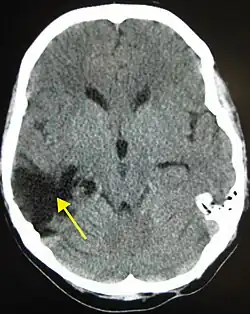

| A CT of the head years after a traumatic brain injury showing an empty space where the damage occurred, marked by the arrow | |